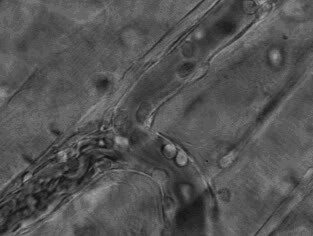

4.免疫细胞也可穿过血管壁奔赴“战场”,向炎症和创伤组织处进军、围剿。

13、人体内寄生虫动态图(小编瞬间觉得奇痒无比)